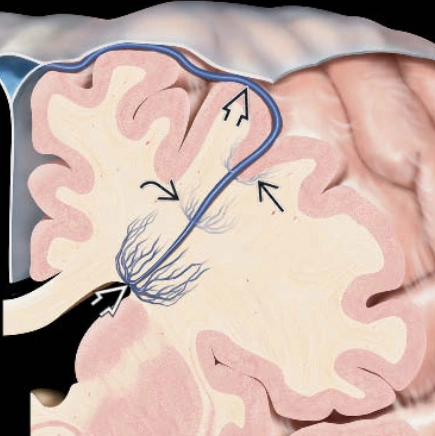

• Bất thường phát triển tĩnh mạch (Developmental Venous Anomaly - DVA)